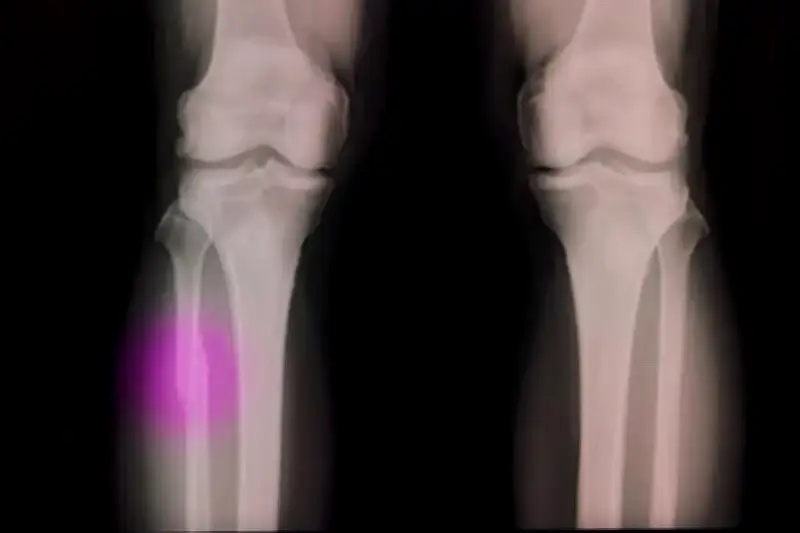

খরগোশের হাড়ে এক সেন্টিমিটার গর্তে এই প্রযুক্তি প্রয়োগ করে ১২ সপ্তাহ পর দেখা গেছে, আঠা ও হাড়ের মধ্যে কোনো ফাঁক নেই এবং মেডিকেল সমস্যা হয়নি। গ্লু গান দিয়ে চিকিৎসা করা প্রাণীদের হাড়ের ঘনত্ব প্রচলিত বোন সিমেন্টের তুলনায় দ্বিগুণের বেশি ছিল।